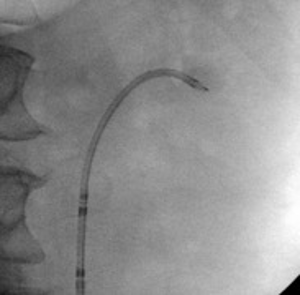

Once endoscopic access has been obtained, TFL lithotripsy is carried out. The energy settings should be adjusted according to the stone’s composition; however, I recommend 20-30 watts in the renal pelvis and intrarenal system; my preferred setting for large stones is 1.5 J with 20 Hz in fragmentation mode in short pulse. For Mini-PCNL I use 365 mc fiber, this allows me to use the same fiber through a flexible ureteroscope in an antegrade manner if needed

Manipulation of the sheath to place the tip near the stone fragments allows for optimal suction. Stone dust and stone fragments are actively suctioned away from the field of view. Then, all calyces and the UPJ are inspected to see that all fragments have been suctioned. Finally, an antegrade nephrostogram is performed prior to stent placement. The stent is placed under fluoroscopic guidance ensuring the distal curl is in the bladder, and the proximal curl is developed endoscopically and confirmed on fluoroscopy.